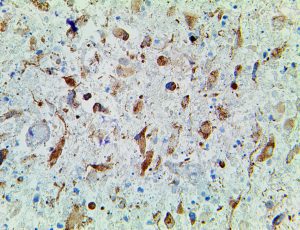

Clinical and laboratory manifestations of HLH include fever, enlarged liver and/or spleen, neurologic dysfunction, coagulopathy, liver dysfunction, cytopenias (i.e., low levels of erythrocytes, leukocytes, and/or platelets), hypertriglyceridemia, hyperferritinemia, hemophagocytosis, and eventually diminished NK cell activity as the immune system becomes progressively paralyzed. HLH can be familial (primary HLH) or secondary to another disease process (sHLH), such as rheumatic disease, in which it is referred to as macrophage activation syndrome (MAS, characterized by elevated ferritin).

This activation induces inflammatory monocytes to highly express IL-6, starting a localized and then systemic cascade effect that results in hyperproduction of IL-6, which accelerates the inflammatory process. Because IL-6 also increases vascular permeability, excessive levels cause blood vessels to become very leaky. This, along with clotting factors released from vascular endothelial cells, stimulates the coagulation cascade, resulting in microthrombosis (tiny clots), which leads to ischemia and tissue death of the kidney, intestines, heart, liver, brain and extremities.